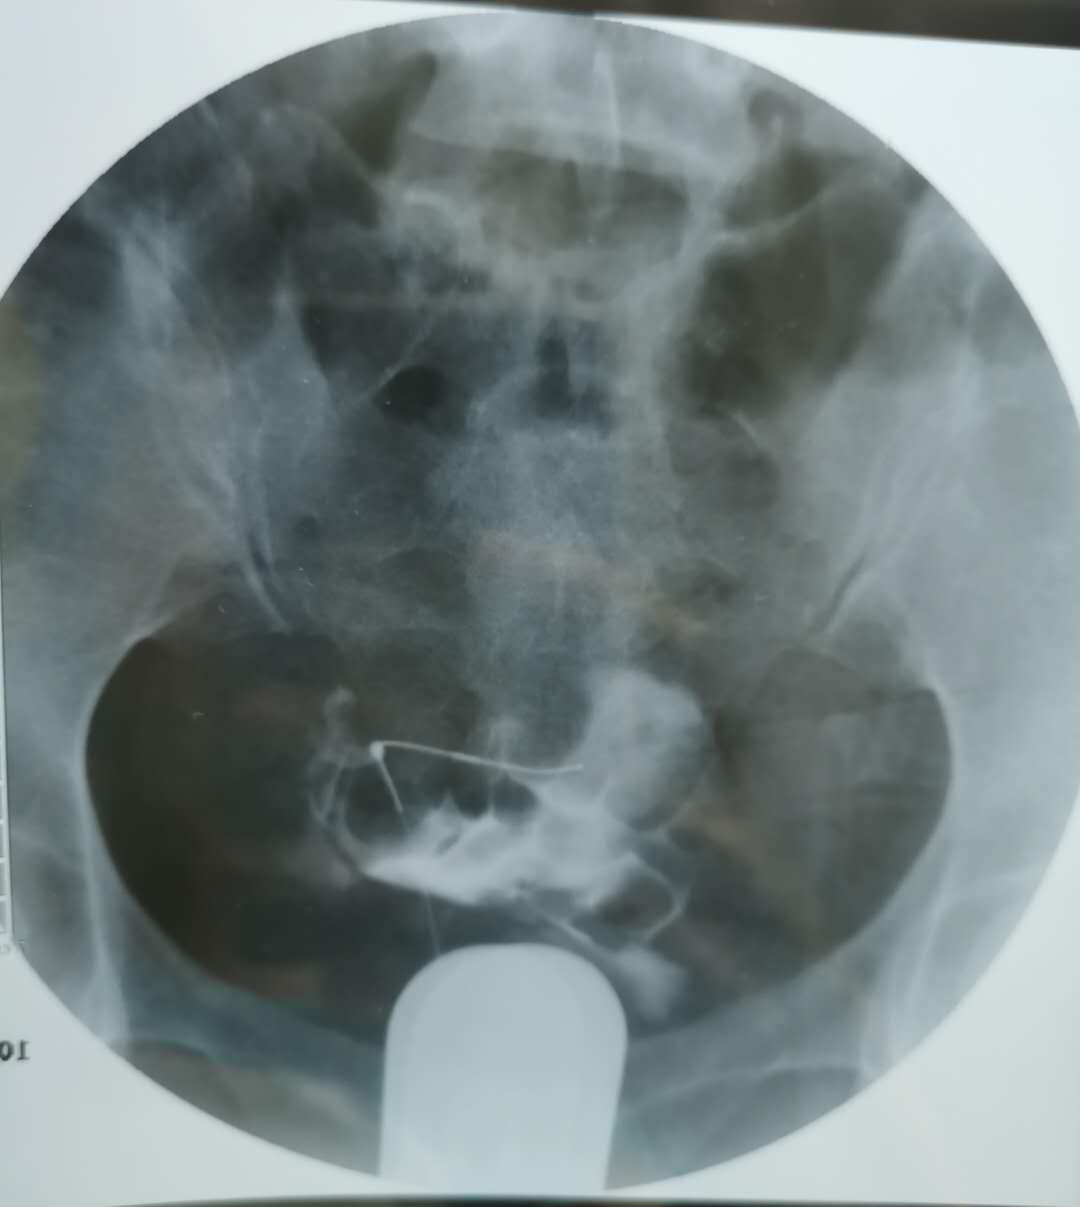

我这个是做了输卵管介入手术,请问输卵管是通了

做完输卵管造影第六天了小腹还是感觉沉甸甸的如

可以热敷腹部,如果有发热,腹痛加剧,白带量多,有异味,随时就医